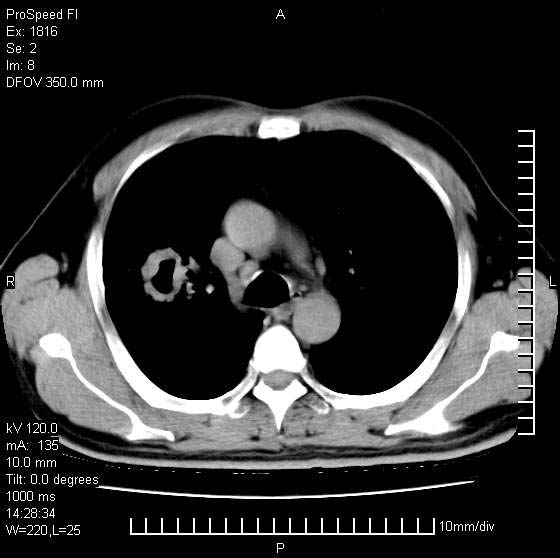

男性,50 ,肺结核9年,咳嗽,胸痛一周。右上肺见一厚壁空洞,周边有点样钙化,胸膜牵拉,洞壁较光整。诊断结核性空洞。有癌性的可能吗? 余肺野无异常,没有上传。

这人应该诊断为肺ca,因为9年的结核密度绝对不是这样!

1.空洞型肺结核;2.周围型肺癌?

洞壁较厚内壁比较光整,两个病灶有关联性,纵隔淋巴结不大,考虑结核性空洞。

结核有可能,肺癌待排。空洞的前上还方见一软组织结节影。

9年的结核应该呈现多形态病灶,该病例只能见到少许纤维索条影,似乎与结核的演变不太相符。空洞内壁不光整,外侧伴有胸膜粘连,考虑癌性空洞可能性大,期待结果。

周围型肺癌不能排除,建议手术治疗。